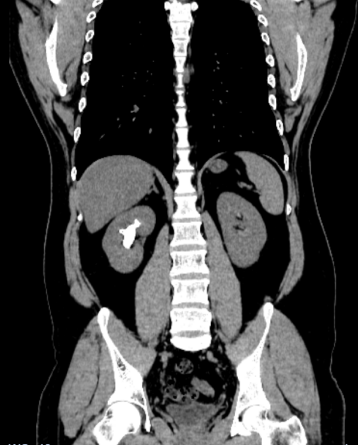

“医生,您帮我看看,我这样的情况能不能不在肾上‘打孔’?”34岁的姚先生拿着自己的CT报告,一脸焦虑地走进市中医医院泌尿外科。报告显示,他的右肾里藏着一颗铸型结石,形状不规则,几乎填满了肾脏空间。外院医生曾建议他做“经皮肾镜碎石取石术”——一种需要在腰部穿刺造瘘的微创手术。一想到术后身上要带着一根肾造瘘管好几天,姚先生犹豫了。泌尿外科副主任杨泽敏仔细阅片后,提出了一个更让他安心的方案——利用先进的高清软镜系统进行“无创清石”,从自然通道进入,碎石的同时直接吸出,体表不会留任何伤口。

效果展示

手术非常顺利,姚先生体内的结石被彻底清除。术后,科室还为他安排了结石成分分析,并开具了个体化的中药汤剂,旨在调理体质,预防复发。从“瞬间清石”到“长期防石”,实现了对泌尿系结石的全程化管理。